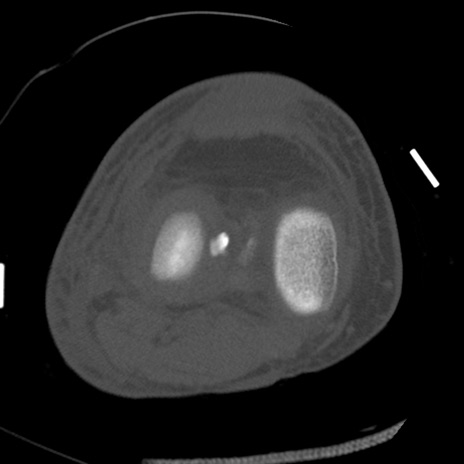

症例28 右膝関節CT(横断像)

右膝関節CT